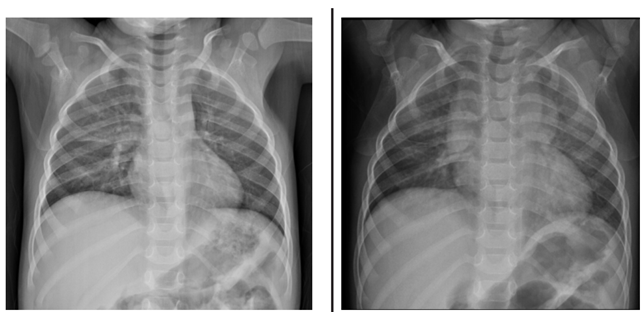

Menino de 2 anos e 6 meses, com história de tosse, dispneia, choro, inapetência e febre há 4 dias, realizou radiografa de tórax (primeira imagem). Após o exame, a mãe recebeu receita médica com medicações para a criança tomar durante 2 semanas, com orientação de repetir a radiografa (segunda imagem) 1 semana após o término do tratamento.

Considerando os dados clínicos e as radiografas acima, analise as afirmativas abaixo e dê os valores Verdadeiro (V) ou Falso (F).

( ) O diagnóstico inicial mais provável é pneumonia, tanto pelos dados clínicos como pela presença de opacidades pulmonares no terço médio à direita na primeira imagem, porém o achado de massa mediastinal na segunda imagem torna a hipótese de pneumonia menos provável.

( ) No exame de controle evolutivo realizado 3 semanas após o primeiro atendimento houve o aparecimento de consolidações pulmonares supra-hilares bilaterais, indicando piora radiológica.

( ) Após a análise das duas radiografas, pode-se chegar à conclusão de que trata-se de um quadro de hiperplasia tímica rebote em criança em processo de recuperação de pneumonia.